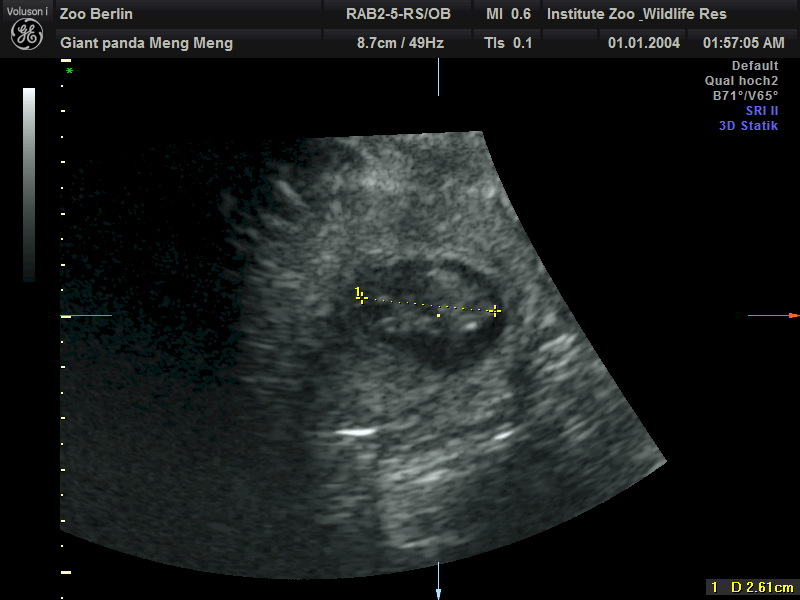

在园方11日上午进行的超声检查中,工作人员清楚地检测到两个熊猫胎儿的心跳。目前两个胎儿身长约2.5厘米。

柏林动物园介绍,根据目前胚胎的大小,如果一切顺利的话,大熊猫双胞胎预计将于8月底出生。